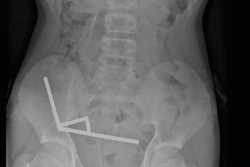

Nouvelle-Zélande : un adolescent opéré après avoir ingéré près de 100 aimants

Source : la1ere.franceinfo.frL’adolescent a avalé près de 100 aimants puissants qu’il avait achetés sur Temu, obligeant les chirurgiens à retirer des tissus de ses intestins. Lire la suite

Publié le : 24/10/2025 24 octobre oct. 10 2025Flux FrancetvinfoL’adolescent a avalé près de 100 aimants puissants qu’il avait achetés sur Te...Source : la1ere.franceinfo.fr